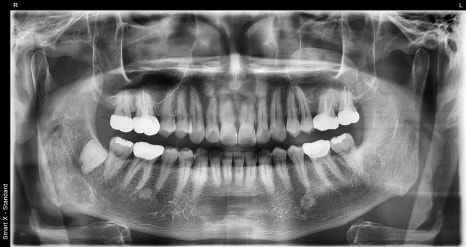

These are the initial X-ray images of a male TMJ patient in his 50s.

Through panoramic and TMJ-specific imaging, abnormal disc positioning (asymmetry) in both TMJs and narrowing of the joint space were confirmed.

The male patient in his 50s visited us with symptoms of “a clicking sound in the jaw and the jaw closing in a zigzag motion every time he chewed.”